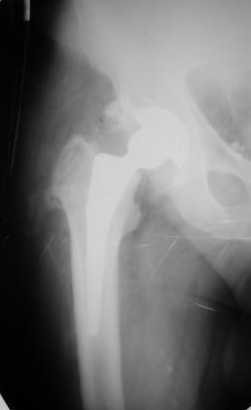

Больной Т. 56 лет, Диагноз: двухсторонний коксартроз 3-4 ст справа, 1-2 ст слева 2.10.08 выполнена операция тотальное бесцементное эндопротезирование. Использовался наружный доступ, положение на боку. Операция протекала без особенностей.

Выполнен послеоперационный ренгеноконтроль в прямой проекции. Рана зажила.

Приходилось ли кому встречаться с такой ситуацией?Вопросы: вросла ли ножка? Какие могут возникнуть сложности с удалением ножки? Нужна ли будет дополнительная трепанация диафиза? И как? Правильный выбор ножка Corail для ревизии в такой ситуации?

Уважаемый Глеб, предложенные снимки впечатлили! Никто не застрахован...